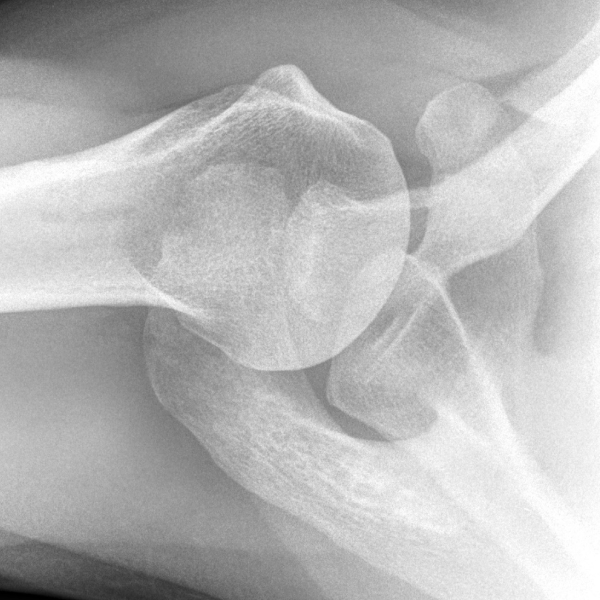

Learn the bony anatomy then test yourself